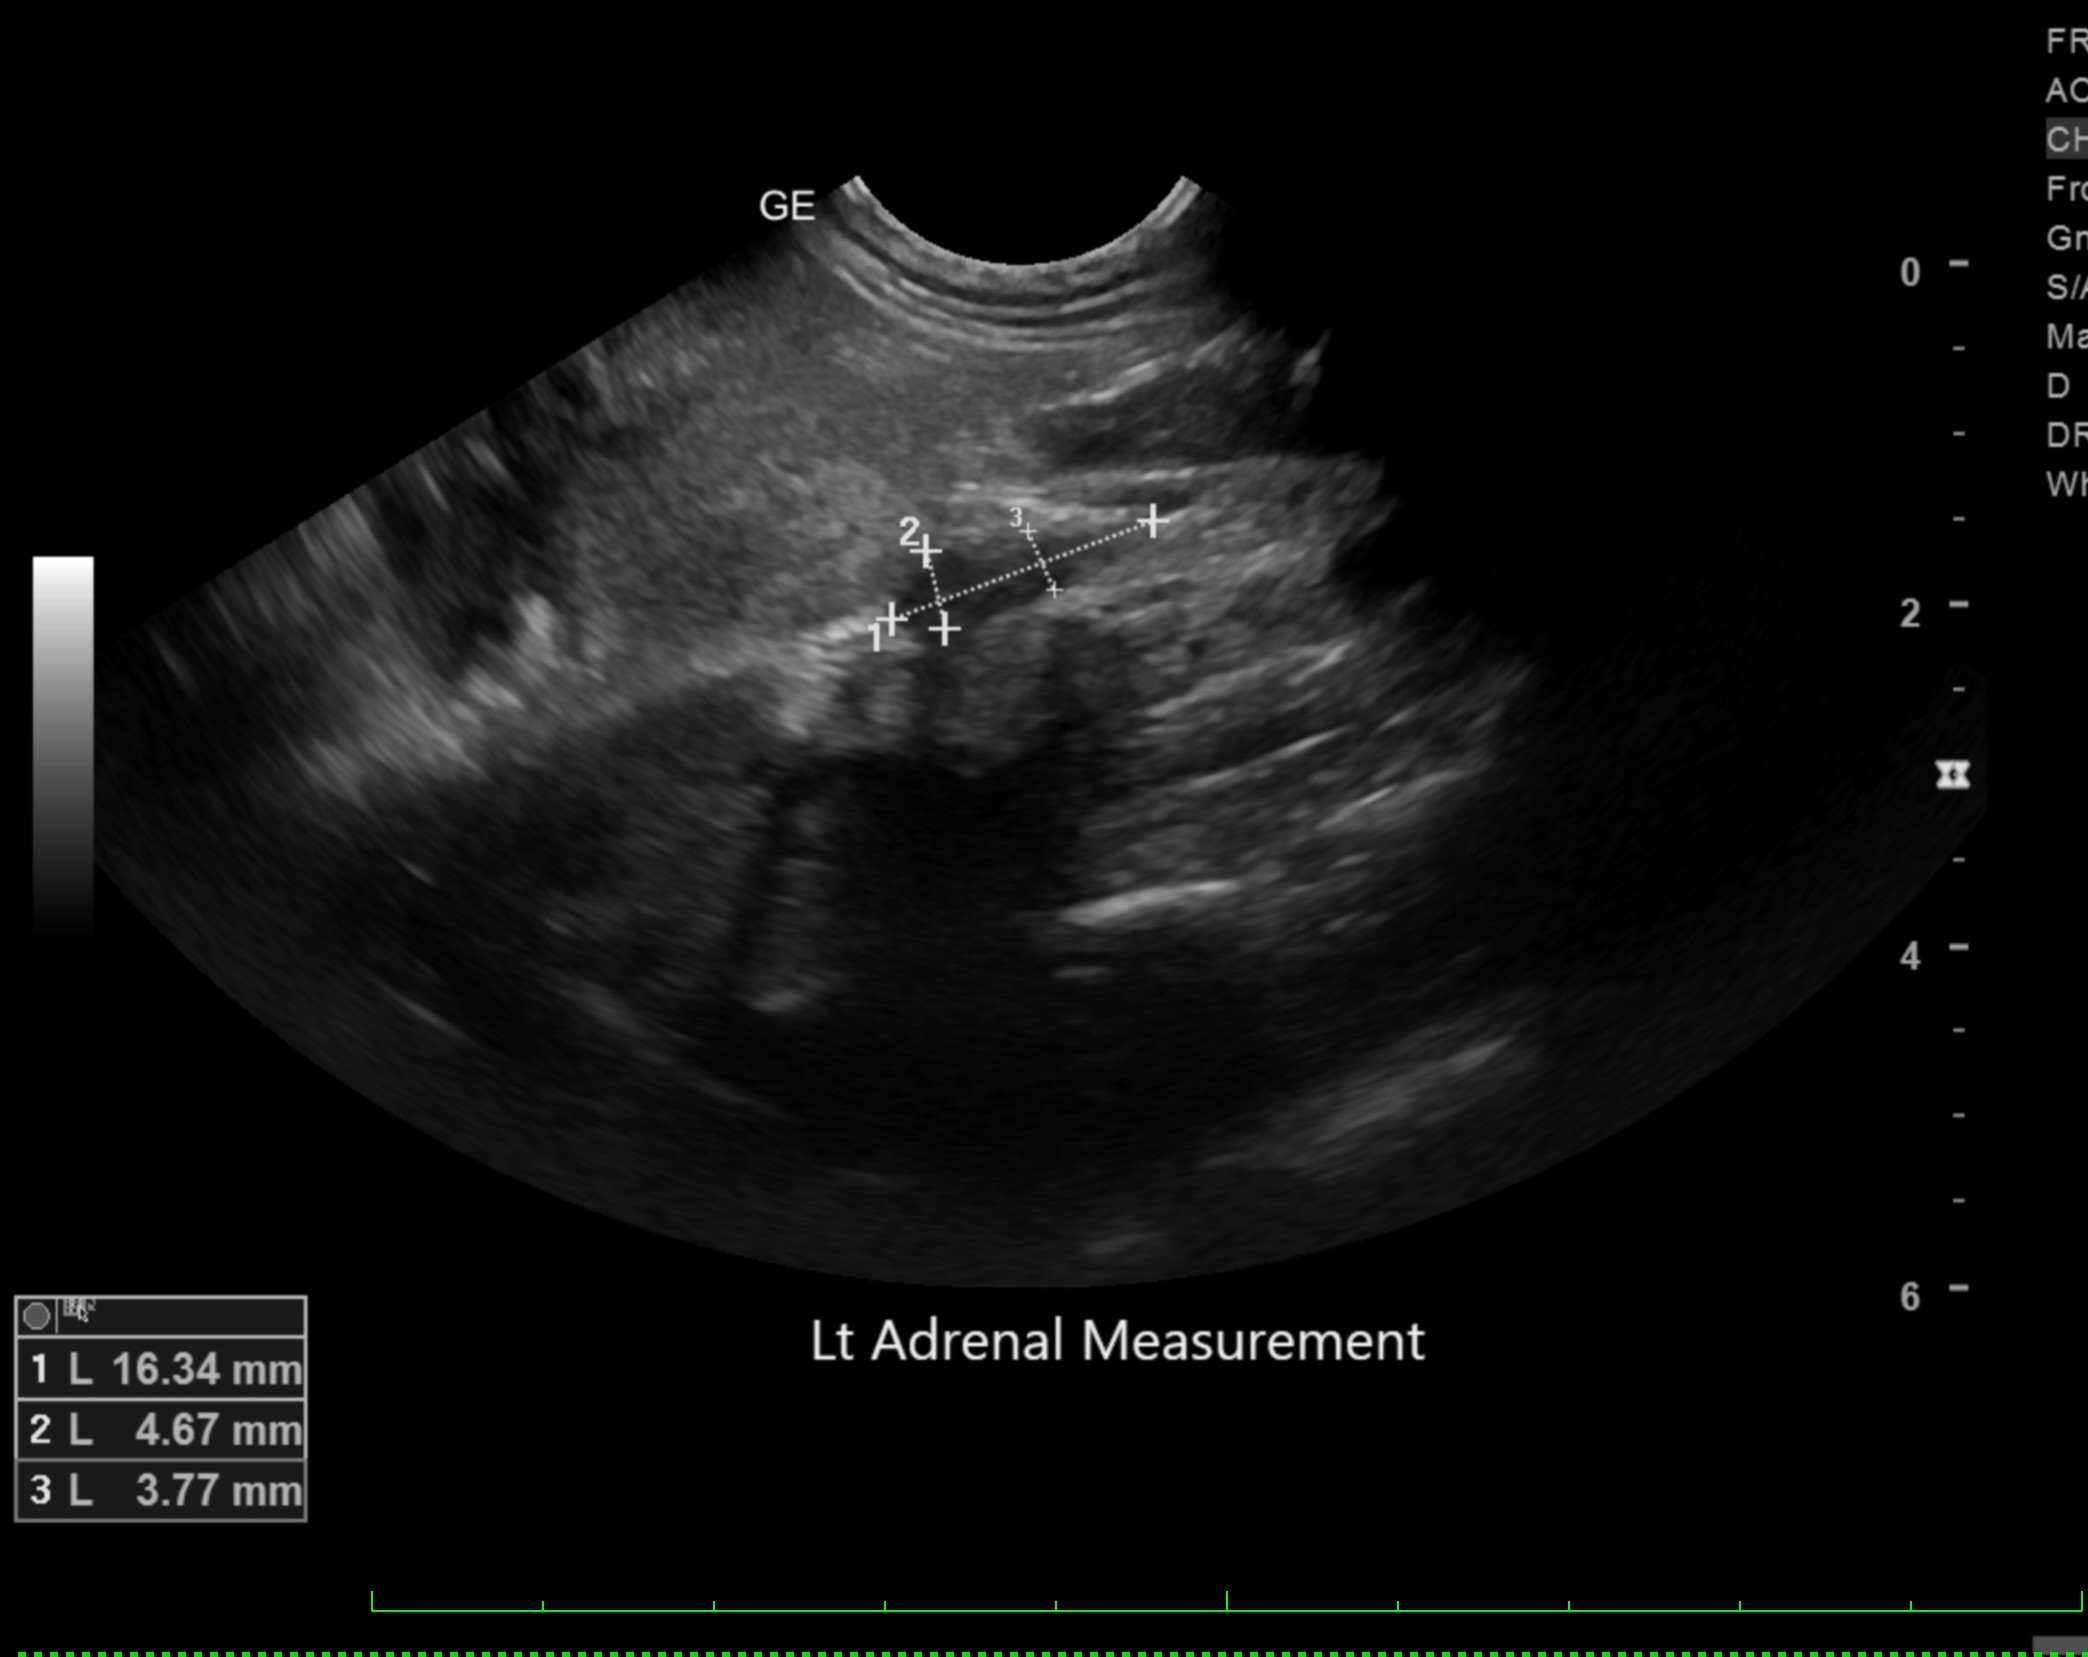

Labwork (fasted): TP 4.5, Alb 2.5, ALP 144, ALT 155, GGT 3, Bili 0.4, Cre 0.3, Cho 51, Amy 266 CBC – HCT 39%, Hgb 12.0 UA – USG 1.030pH 6, 1+ bilirubin, WBC 4-10/hpf, rods 26-50/hpf Negative Accuplex Bile Acids: Pre 299.2, Post-meal – 90.7